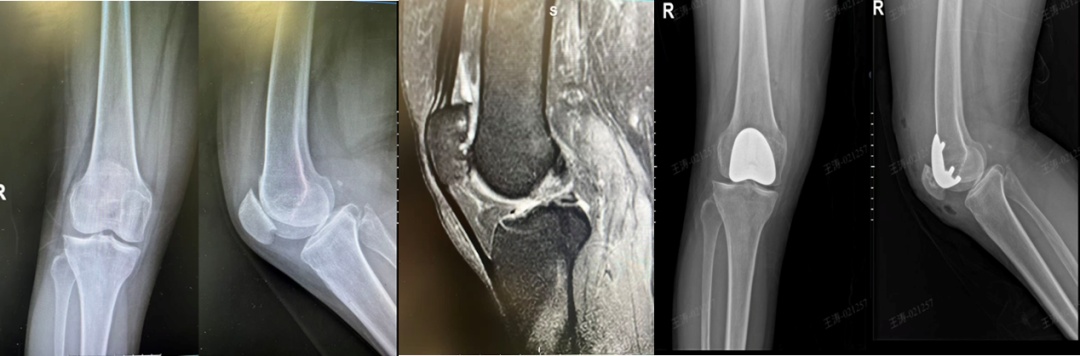

专注解决“膝前痛”,常见于上下楼、下蹲时疼痛加剧,而其他间室完好的患者。技术精髓在于仅对髌骨和股骨滑车表面进行置换,保留了膝关节内外侧的健康结构及所有韧带。

核心优势在于针对性根除特定痛苦,术后患者上下楼梯、起身下蹲的疼痛得到明显缓解,同时避免了为局部问题而置换整个关节的“过度治疗”。这是解决孤立性髌股关节炎的终极微创方案,能有效恢复膝关节伸屈功能,缓解特定疼痛。